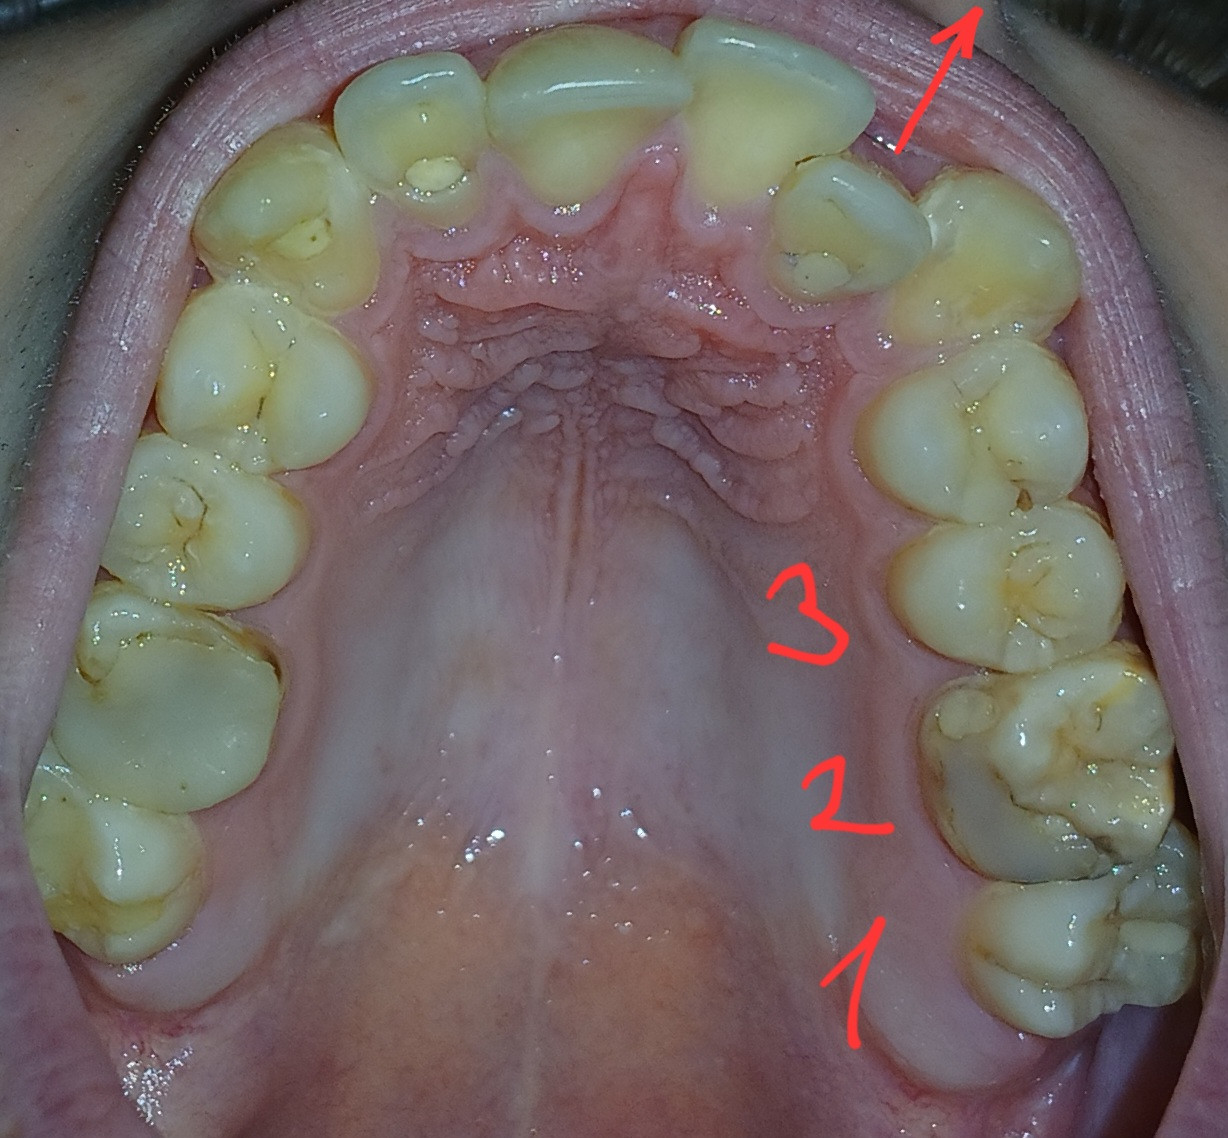

Какой лучше всего удалить? Например 2 (на фото после зуба мудрости) выглядит хуже чем остальные, но я читал что удаляют зубы мудрости (1 на фото). Имеет ли значение какой именно зуб удалять с точки зрения наилучшего движения?

Может быть очевидно нужно просто удалить плохой зуб 2, а я тут думаю.

Здравствуйте. По фото видно скученность зубов в боковом отделе, и действительно зуб №2 (второй от конца на фото) выглядит более разрушенным, чем зуб мудрости (№1).

Если зуб мудрости (№1) полностью прорезан, не мешает прикусу и в хорошем состоянии то тогда целесообразнее удалить зуб №2, так как он повреждён и, скорее всего, не имеет большого прогноза на восстановление. Однако если зуб мудрости растёт под углом или не участвует в жевании тогда может быть показано его удаление.

Решение зависит от угла наклона зубов, прикуса, объёма необходимого пространства, состояния каждого конкретного зуба.

Удалить проблемный зуб №2 (если он действительно не подлежит лечению), после чего оценить изменения. Если улучшений не будет то по возможности проконсультироваться в с ортодонтом. Если бюджет ограничен то хотя бы сделайте панорамный снимок (ОПТГ) и покажите его врачу.